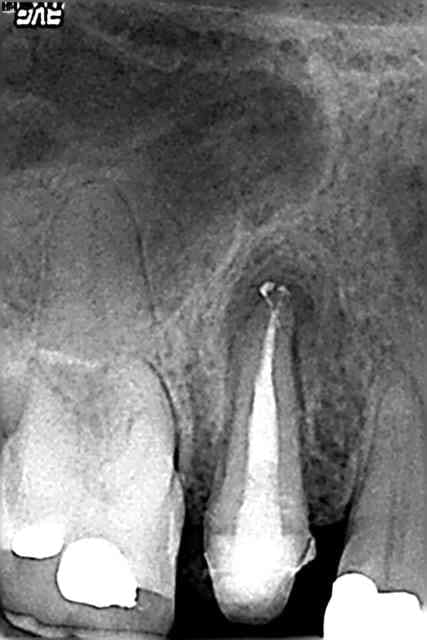

une reprise d'endo du jour pr le plaisir:)

2 ans 4 mois,un amour!